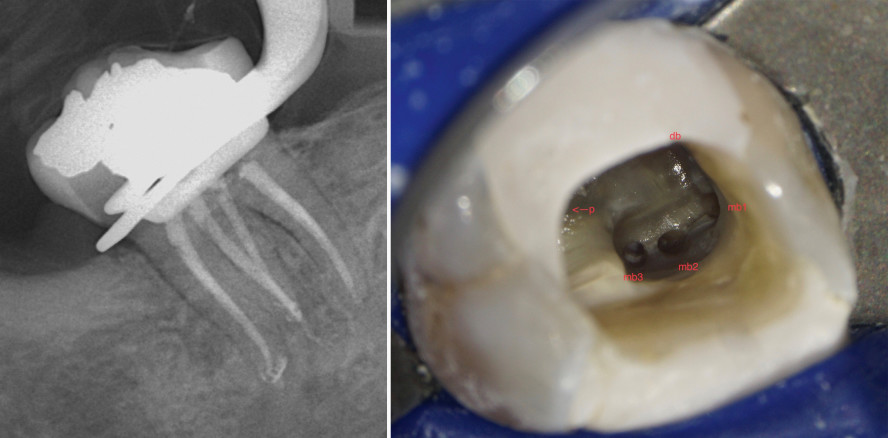

Ein Patient stellte sich mit Schmerzen im linken Unterkiefer Regio 37 vor. Die klinische Symptomatik wies bereits auf die Notwendigkeit einer Wurzelkanalbehandlung hin. Das angefertigte Röntgenbild ließ keine Beurteilung der distalen Wurzel zu. Dagegen konnte ein erweiterter Parodontalspalt sowie eine leichte apikale Aufhellung an der mesialen Wurzel nachgewiesen werden (Abb. 5).

Nach Schaffung der Zugangskavität, dem Preflaring und der Gleitpfad-Erstellung bis zum Apex erfolgte die weitere Aufbereitung der Kanäle. Ab einer Größe von ISO 15 kann eine Messaufnahme getätigt werden. Wird die Messaufnahme mit Guttaperchapoints anstatt Feilen durchgeführt, sollte größer aufbereitet werden, um den Apex zu erreichen. Alternativ sollte ein geringerer Taper der Guttapercha im Vergleich zur Arbeitsfeile genutzt werden.

In diesem Fall wurden in drei Wurzeln auch drei Wurzelkanäle gefunden und bis zum Apex aufbereitet (Abb. 6). Nach weiterer Aufbereitung und gründlicher schallaktivierter Spülung der Wurzelkanäle wurde mesial ein dritter Kanal aufgefunden. Dieser liegt häufig zwischen dem mesiolingualen und mesiobukkalen Kanal in einem mehr oder weniger tiefen Isthmus. Hier lohnt die Freilegung mittels Munce Discovery Burs oder EndoTracer.

Nun erfolgte das Füllen der Kanäle mittels biokeramischem Sealer und warm vertikal applizierter Guttapercha.